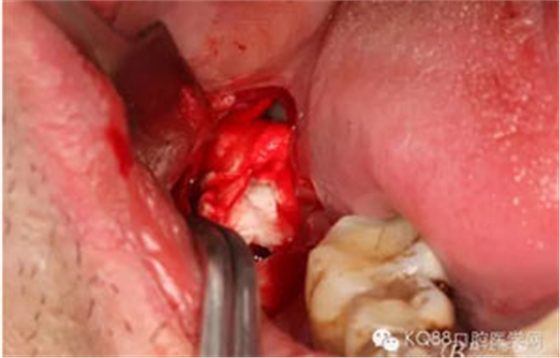

圖7.高速牙鉆去骨。逐漸可見48的牙冠

圖8.刮除牙冠表面的肉芽組織后,可見48 的牙冠